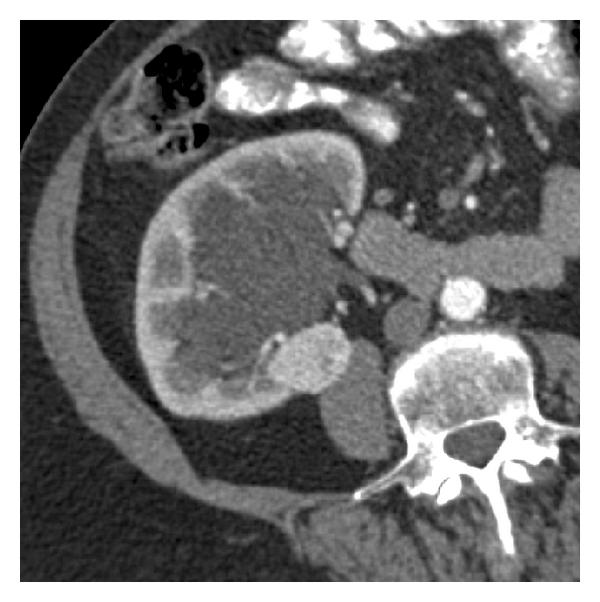

The imaging characteristics of RCC are extremely varied, with masses ranging from cystic to solid, from homogeneous to heterogeneous and necrotic, from small to large, and from localized to extensive. The typical CT appearance of small RCC is a homogeneously isodense/hypodense mass, noncalcified, with an attenuation value of 20 HU or more, that enhance avidly and early with contrast medium (see Figure 8) [23]. The early-stage contrast enhancement is believed to be caused by tumor angiogenesis. However, a small proportion of RCC are hypovascular, and the amount of enhancement may be minimal. Small RCC with a predominantly cystic growth pattern, necrosis, or calcifications (peripheral curvilinear or punctate central) are uncommon. Areas of fat attenuation can be present within renal cell carcinomas, but are uncommon in small tumors.

(a)

(b)